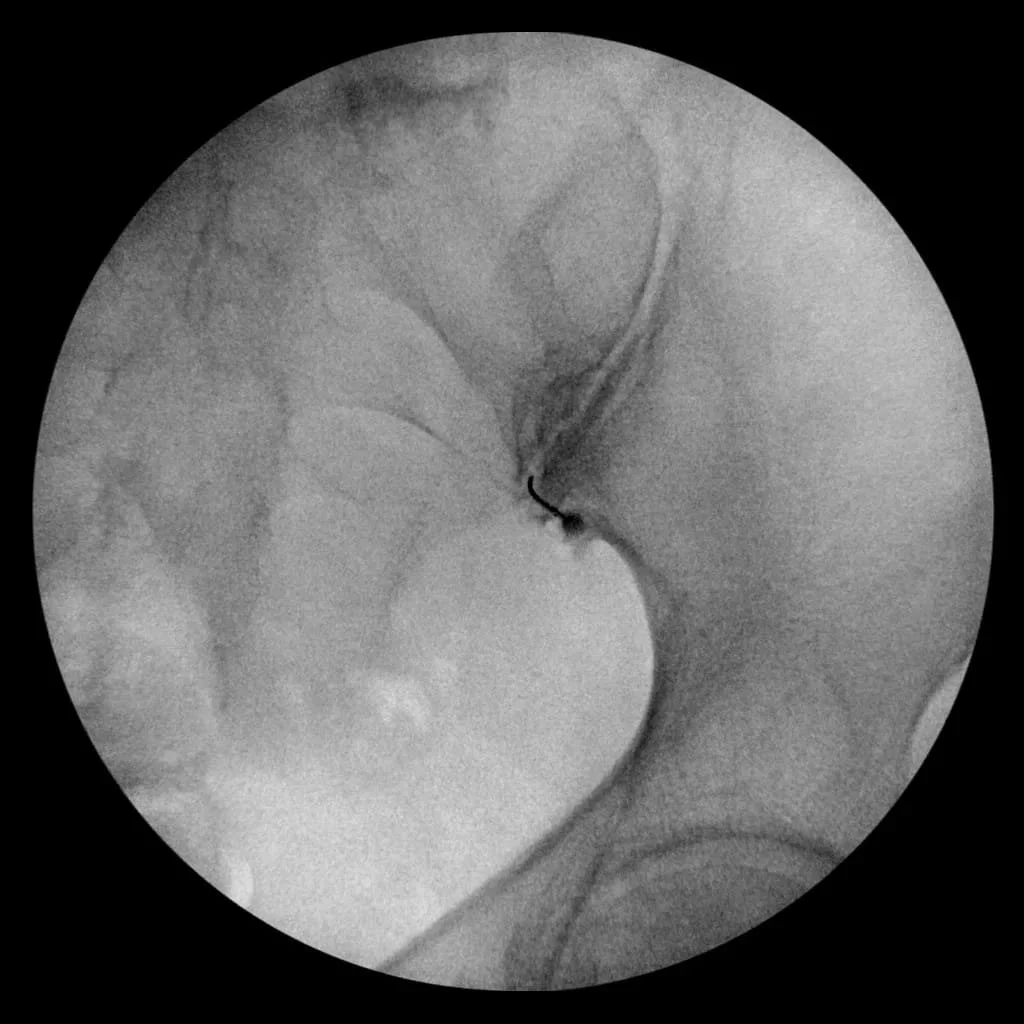

• Image-Guided Injections Corticosteroids and local anesthetic are precisely injected into the SI joint to reduce inflammation. This can relieve pain for weeks or months and help confirm the diagnosis.

Fluoroscopic-guided sacroiliac joint injection

Sacroiliac joint injection procedure for SI joint pain relief at Sobel Spine and Sports Phoenix AZ